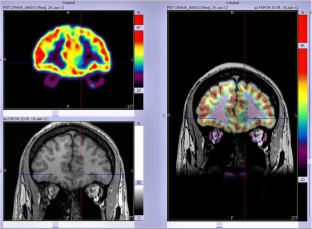

We analysed 18F-FDG PET scans from 103 consecutive patients (52 males, 7–65 years old) with histologically proven FCD2. PET and MRI data were first reviewed by visual analysis blinded to clinical information and FCD2 location. The additional value of electroclinical data and PET/MRI coregistration was assessed by comparison with pathological results and surgical outcomes.

Visual analysis of PET scans showed focal or regional hypometabolism corresponding to the FCD2 in 45 patients (44%), but the findings were doubtful or misleading in 37 patients and negative in 21. When considering electroclinical data, positive localization was obtained in 73 patients, and this increased to 85 (83%) after coregistration of PET and MRI data. Under the same conditions, MRI was positive in 61 patients (59%), doubtful in 15 and negative in 27. The additional value of PET was predominant in patients negative or doubtful on MRI, localizing the FCD2 in 35 patients (83%). Interobserver agreement correlated with the grade of hypometabolism: it was good in patients with mild to severe hypometabolism (82–95%), but moderate in those with subtle/doubtful hypometabolism (45%). The main factors influencing positive PET localization were the grade of hypometabolism and the size of the FCD2 (P < 0.0001). Misleading location (nine patients) was associated with a small FCD2 in the mesial frontal and central regions. Following limited cortical resection mainly located in extratemporal areas (mean follow-up 5.6 years), a seizure-free outcome was achieved in 94% of patients, including Engel’s class IA in 72%.

In this series, 18F-FDG PET contributed to the localization of FCD2 in 83% of patients. This high localizing value was obtained by integration of electroclinical data and PET/MRI coregistration. This approach may help improve the surgical outcome in extratemporal epilepsy, even in patients negative on MRI.